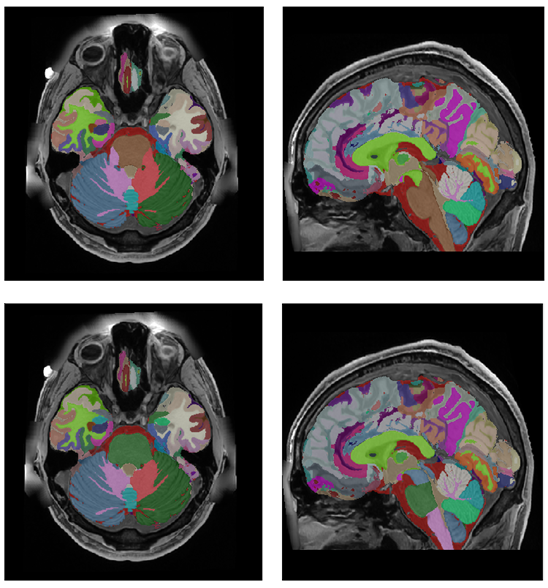

Data Records

After the whole integration process, we generate the last version at multiple scales (substructure/structure/tissue/organ). Figure 12 shows the holiAtlas templates for T1w, T2w and WMn MRI and the corresponding labels. Label definitions and relations among different scales can be inspected in the appendix section. The generated holistic atlas jointly with the multiscale label definitions is publicly available through the following link: https://volbrain.net/public/data/holiatlas_v1.0.zip. The package contains several NIfTI files (.nii) with the volumes and their corresponding segmentations at different scales, and an Excel file describing each label and their relationship among scales.

Specifically, there are three files corresponding to the averaged anatomy for each modality (T1, T2 and WMn). Besides, there are 4 segmentation files including labels at different scales (intracraneal cavity mask, tissue, structure and substructure). All the volumes are located at MNI152 space [9] (0.125 mm3).

Refer to caption

Figure 12: From Top to bottom: Average T1w MRI template, average T2w MRI template, average WMn MRI template and majority voting atlas labels at substructure resolution.

holiAtlas represents a comprehensive, multimodal, and ultra-high-resolution MRI-based atlas of the human brain anatomy. This atlas was constructed by fusing data from various local protocols with corresponding scales, resulting in a densely labeled protocol. The creation involved averaging images and segmentations from 75 healthy subjects, employing T1w, T2w, and WMn MRI contrasts at a 0.125 mm3 resolution. This atlas offers a holistic view of the brain’s anatomy at different levels and scales, providing a valuable resource for segmentation methods, research, and educational purposes.